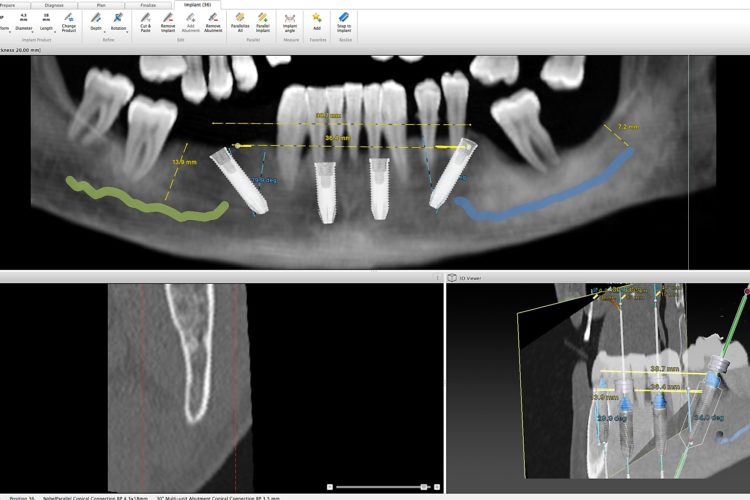

Caso Clínico:  Reabilitação total bimaxilar com 10 implantes e 2 próteses híbridas Descrição: Paciente com 65 anos residente em Macau que pretende uma reabilitação total com implantes no prazo máximo de 8 meses. O tratamento constituíu na extração de todas as peças dentárias, colocação de 6 implantes no maxilar superior e 4 no maxilar inferior culminando